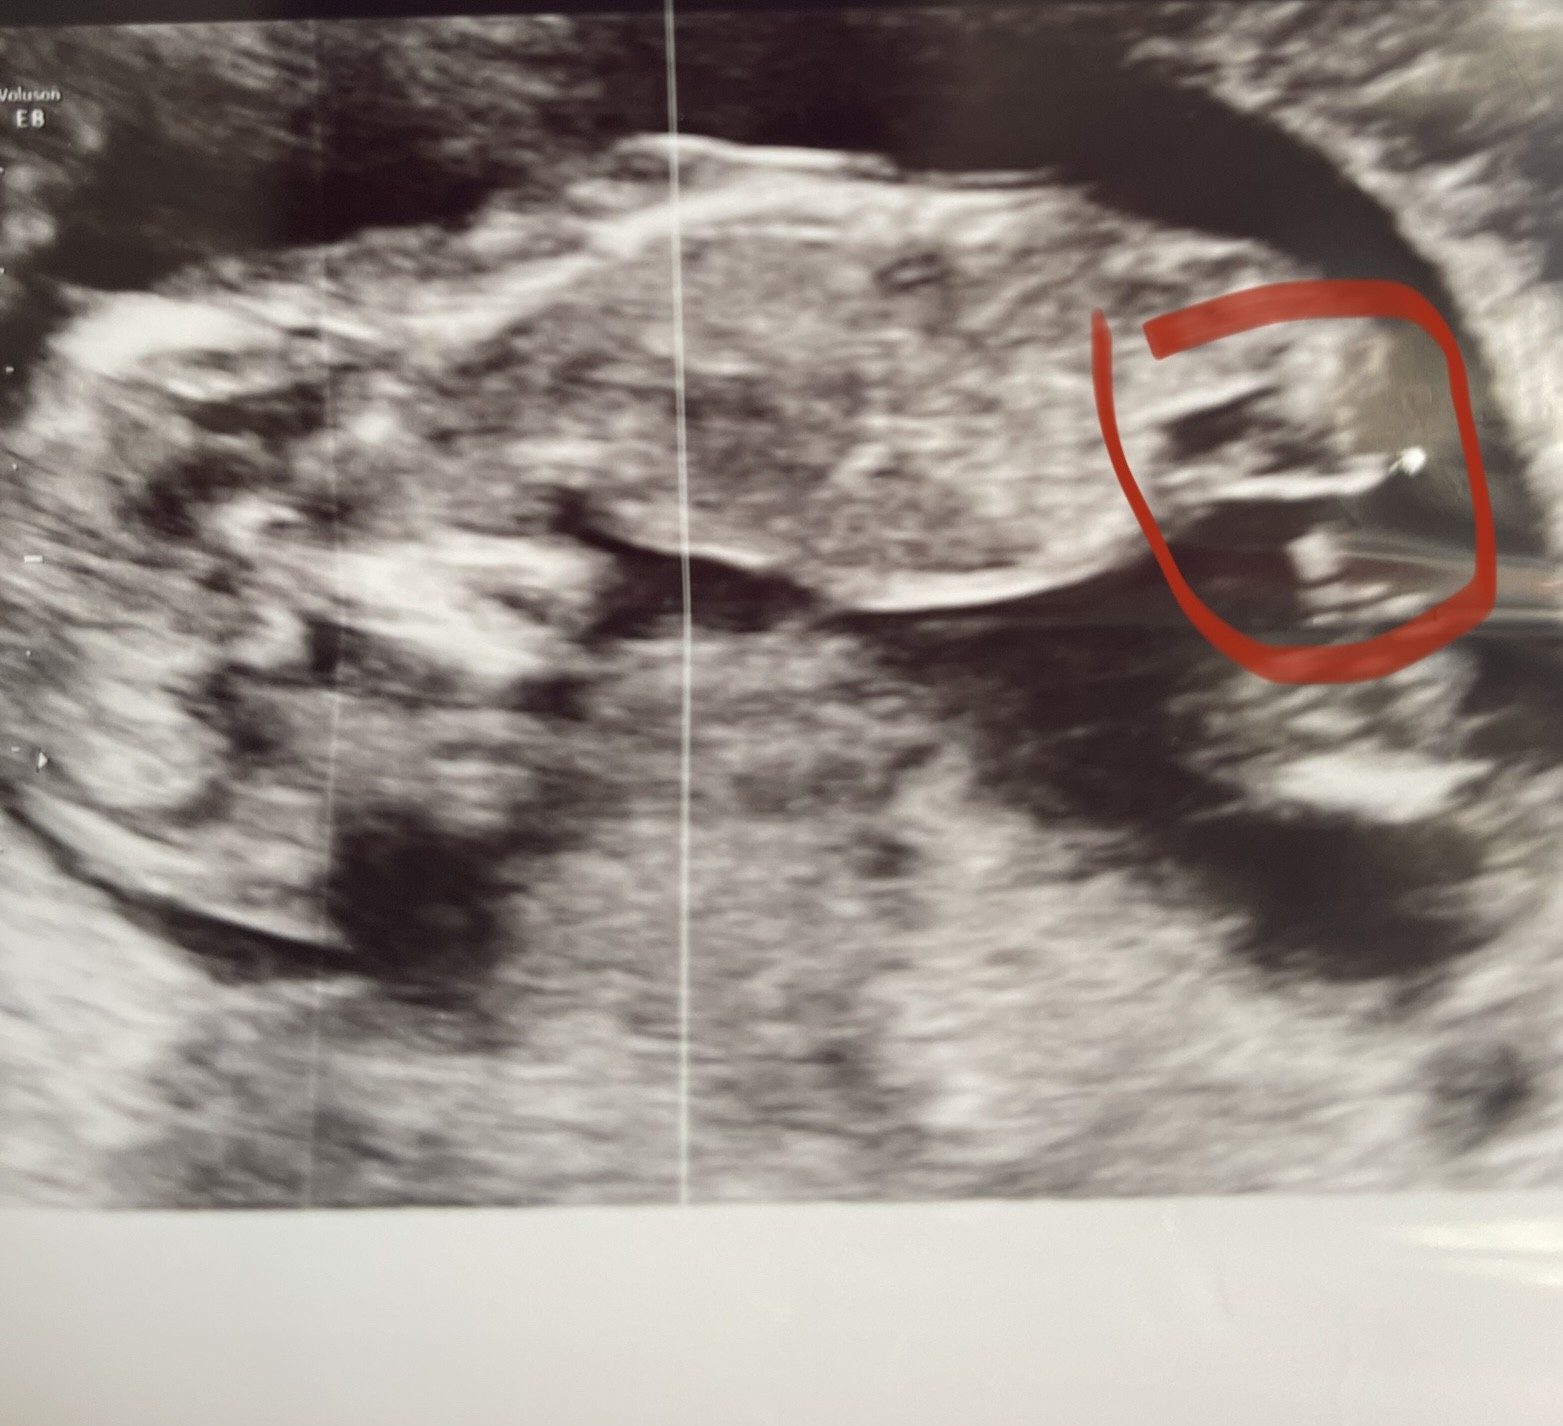

Na ostatniej wizycie ginekolog zasugerował płeć na podstawie wyrostka płciowego. Oczywiście zaznaczył, że nie jest to na 100%, ale wstępnie widzi dziewczynkę

Czy Wy też to widzicie?

Czy u którejś z Was był taki przypadek, że wyrostek też był poziomy względem kręgosłupa (dziewczynka), a już na kolejnych badaniach odstawał do góry i był jednak chłopiec?